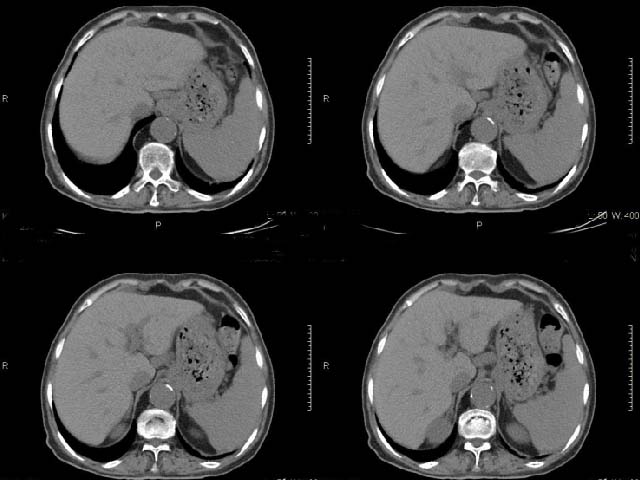

女,69岁,浑身乏力,腹泻半年余,无腹疼,排泄物中含有脂肪球,抗炎治疗一周仍不缓解,来我院检查发现明显低钾血症,给予补钾(氯化钾)一周后,血钾恢复正常,经化验检查,尿钾持续明显高于正常,临床考虑患者不仅消化道失钾,还伴有泌尿系统失钾,故进行ct增强检查看肾上腺是否有病变。ct表现为胰腺肥大,而且体尾部强化较弱,明显呈稍低密度,胰尾见有更低密度,而且胰腺与周围组织的脂肪间隙不清,大血管周围似乎有包绕现象,患者是否有过胰腺炎病史,家属说不清楚;而双侧肾上腺大小形态,本人认为未见异常,本人倾向于考虑:慢性胰腺炎伴假性囊肿,不排除胰腺占位可能;但是不知怎么解释持续尿钾现象。请大家发表高见!

平扫

动脉期

静脉期